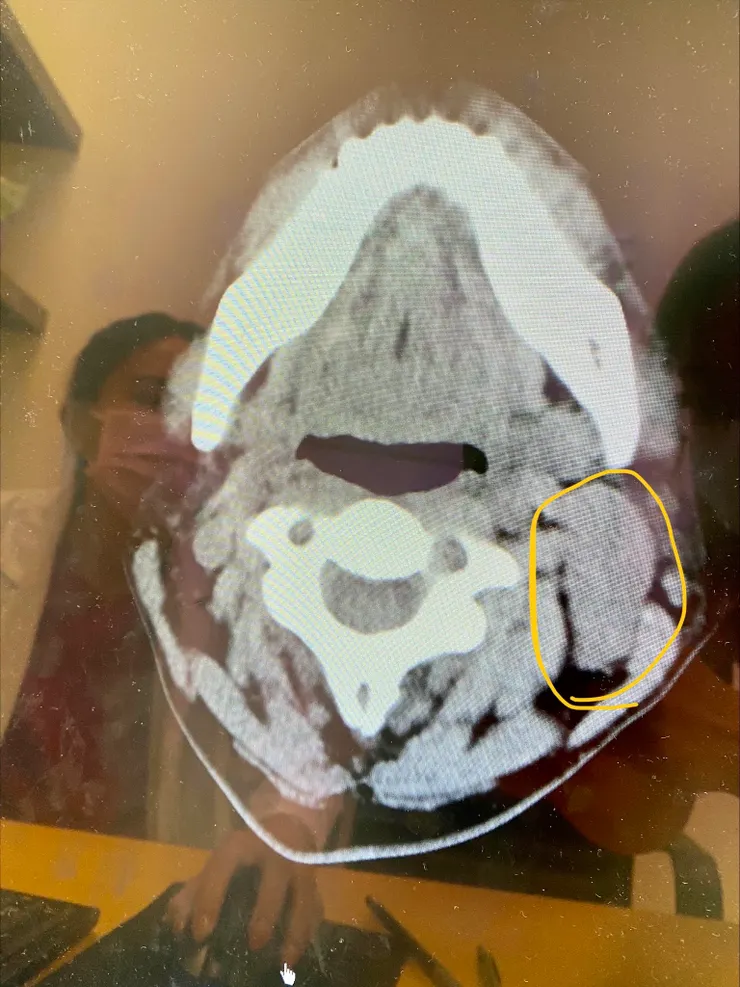

由於牽涉到顏面神經事關重大,因為顏面神經損傷會造成口歪嘴斜,這讓卡蘿相當猶豫,後來經過好朋友介紹到臺北醫學大學附設醫院再度確認病情,醫師安排電腦斷層檢查,看完 CT 片後再度確認是腮裂囊腫,而腮裂囊腫不會因用藥而消失,有可能會因為反覆發炎而愈來愈大,一勞永逸的作法就是開刀摘除腫塊,手術完全切除後腮裂囊腫復發機會極低,重點中的重點是醫師說卡蘿這個腮裂囊腫的位置不會動到顏面神經,所以不用擔心😍。

電腦斷層檢查 CT 可以清楚看到腫塊的位置和大小